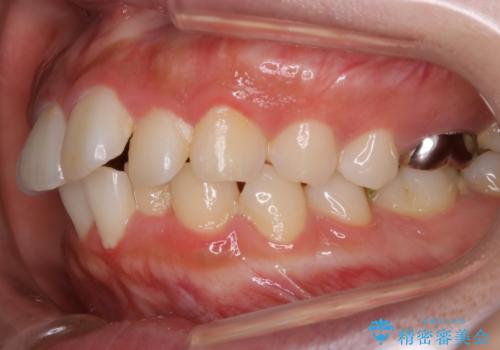

- 歯のガタつきと口元の突出感を主訴に来院されました。

装置の希望がインビザラインだったため、非抜歯でインビザラインの特徴を最大限に生かして行う矯正治療を選択しました。

一般的に口元を下げるための治療というと抜歯矯正を思い浮かべる方が多いかと思います。そもそもガタつきを治したり歯を引っ込めるためのスペースの作り方には大きく分けて4種類の方法があります。

①抜歯 ②歯列の幅の拡大 ③IPR(歯の幅を削って小さくする) ④歯の後方移動 です。

インビザラインの登場により抜歯以外の3種類の方法を効率よく活用することができるようになりました。

そのため、非抜歯でも口元の環境が改善するケースがあります。